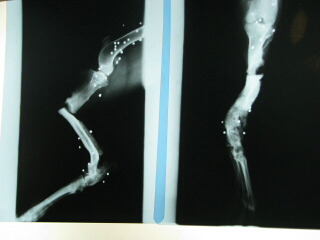

Χάρη στην οικονομική σας συμβολή, χειρουργήθηκε τελικά ο Τόνυ στις 20 Νοεμβρίου. Όπως βλέπετε στις ακτινογραφίες, τα πίσω του πόδια είναι γεμάτα σκάγια. Δύο από αυτά είχαν εισχωρήσει στην άρθρωση του γονάτου κι έπρεπε να βγουν. Είχε πυροβοληθεί από τον γενναίο κυνηγό πισώπλατα.